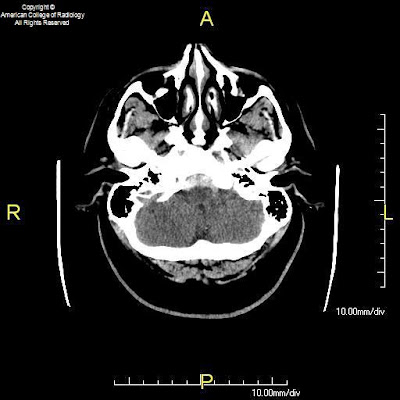

Figure 1, Figure 2, and Figure 3: Axial CT images of the brain demonstrate SAH in the premedullary, prepontine, suprasellar, and interpeduncular cisterns.

Diagnosis: Benign perimesencephalic SAH

The classic variety of non-aneurysmal SAH is known as benign perimesencephalic SAH or pretruncal nonaneurysmal SAH. As the name implies, the hemorrhage is situated around the midbrain and anterior to the brainstem in the ambient, interpeduncular, and prepontine cisterns. The term “benign” refers to the fact that after recovery from the initial episode, there is no increased risk of repeat hemorrhage. Cerebral vasospasm is less likely in these patients, but does occur. Hydrocephalus also remains a possibility during the acute phase. Although not clearly understood, one proposed mechanism of benign perimesencephalic SAH is rupture of the venous plexus anterior to the pons (the anterior pontomesencephalic plexus). This is postulated to occur as a result of increased venous pressure from strenuous activities such as exercise. Intramural hematoma of the basilar artery and rupture of a basilar perforating artery have also been suggested as alternate hypotheses.